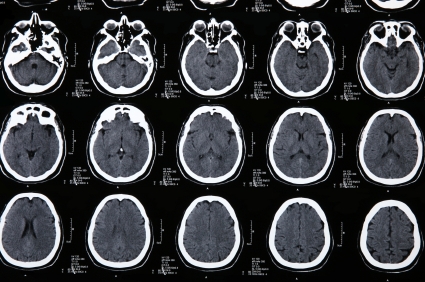

ДИАГНОСТИКА

Наиболее достоверным достоверным методом диагностики является люмбальная(спинномозговая пункция)и анализ ликвора.

Компьютерная м магнитно- резонансная томографии также инормативны.Электроэнцефалография ,эхоэнцефалография,осмотр глазного дна

Медицинские процедуры, проводимые при заболевании энцефалит: Спинальная пункция, Компьютерная томография, Магнитно-резонансная томография, Электроэнцефалограмма